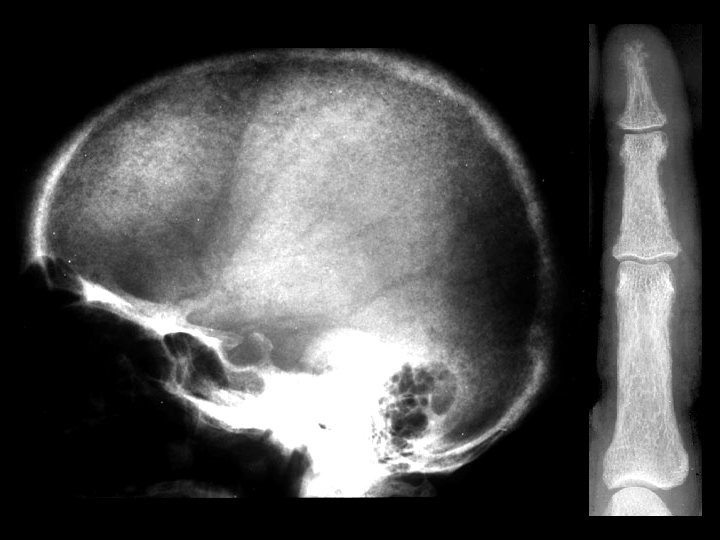

Hyperparathyroidism • Findings: – “salt and pepper” skull – Osteopenia with course trabecula – Subperiosteal resorption • ddx: – NONE! – This is an Aunt Minnie!

Eosinophilic Granuloma • Findings: – Well-defined lytic lesion in the frontal skull crossing the diploic space – Overlying scalp swelling – Positive bone scan • ddx: – Osteomyelitis – Metastasis